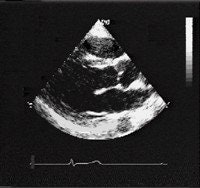

![]() |

| The same 17-year-old asymptomatic basketball player. Coronary artery angiography in the left oblique anterior view. Selective injection of contrast medium in the left sinus of the Valsalva confirms that the right coronary artery originates from the left sinus just anterior to the left coronary ostium. Zeppilli P, dello Russo A, Santini C, Palmieri V, Natale L, Giordano A, Frustaci A, "In vivo detection of coronary artery anomalies in asymptomatic athletes by echocardiographic screening" (Chest, 1998 Jul;114(1):89-93). |